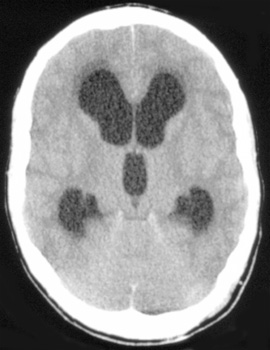

Hydrocephalus, a problem with the ratio of production of CSF to its reabsorbtion, is most frequent in children. Communicating hydrocephalus is the most common and is due to arachnoid villi and subarachnoid space obstruction. Obstructive hydrocephalus is less common but may occur as a result of the following:

![]() ![]() ![]() In these sections from the same patient notice the enlagement of the ventricles and cisterns that occurs with hydrocephalus. |